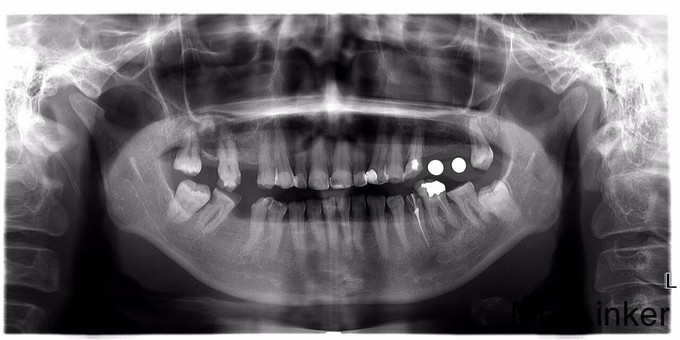

多颗牙缺失的修复治疗

左右后牙均有缺失,咀嚼效率低,要求镶牙